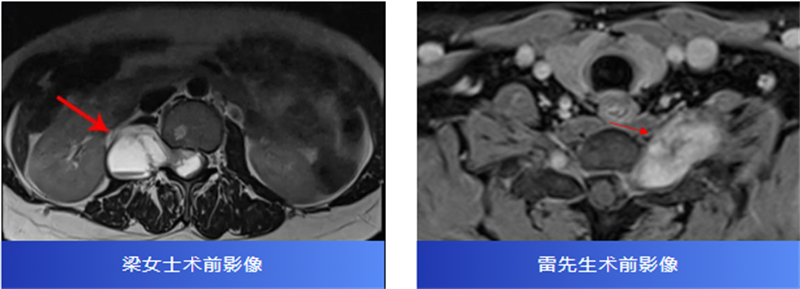

后來,經(jīng)過腰椎磁共振檢查,才發(fā)現(xiàn)原來是椎管內(nèi)長了一個腫瘤,壓迫著神經(jīng),并向外生長,延伸到了右腎附近,情況十分復雜。

兩名患者轉(zhuǎn)診至柳州市人民醫(yī)院后,脊柱外科主任、主任醫(yī)師胡巍博士迅速組織醫(yī)學影像科、麻醉科等多學科會診。團隊對腫瘤病變范圍、與神經(jīng)的毗鄰關(guān)系進行周密評估,為每位患者制定個體化手術(shù)方案。

術(shù)中,在顯微鏡輔助下,醫(yī)生精細分離腫瘤與神經(jīng)組織,小心翼翼解除壓迫,最終切除了腫瘤。病理報告也帶來好消息:兩人均為良性神經(jīng)鞘瘤。

術(shù)后,梁女士的腰腿痛消失了,雷先生的頸肩脹痛也得到了緩解。兩位患者都保住了正常的神經(jīng)功能,步入康復的新階段。